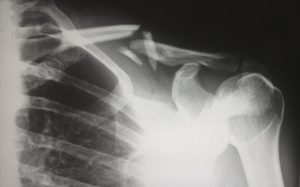

Finnish medical technology developer Bioretec has made history with its RemeOs metal screws, which hasten the healing of broken bones by helping to properly secure them during the often-lengthy mending process. The company says that the inserts are the very first bioresorbable metal implants to ever earn approval from the FDA. The metallic properties of the screws makes them stronger, with added rigidity and hardness, compared to more common polymer-based bioresorbable implants. Moreover, the screws can be leveraged in heavy load-bearing applications, making them a viable option for feet or ankle bone placement.